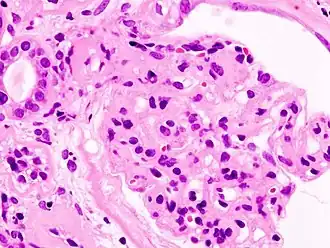

In het gevorderde stadium van het diagnostisch proces, waarbij eenvoudig en specifiek laboratoriumonderzoek niet hebben geleid tot opheldering van de oorzaak van het nefrotisch syndroom kan besloten worden tot het nemen van een nierbiopt, zodat het primair nefrotisch syndroom histologisch vastgesteld kan worden.

Deze diagnostische procedure leidt soms tot complicaties, waarvan een bloeding de belangrijkste is. Ongeveer 3–10% van de patiënten heeft na de ingreep tijdelijk wat bloedverlies van enige betekenis, waarbij in slechts 0,1–0,3% van de gevallen ook daadwerkelijk transfusie noodzakelijk is. De sterfte door dit onderzoek is 0,08–0,12 procent. Het van tevoren in kaart brengen van risicopatiënten (oncorrigeerbare hypertensie, bestaan van hydronefrose, positieve familie-anamnese voor stollingsstoornissen, acenocoumarol- of acetylsalicylgebruikers) en het vooraf controleren of er een normale bloedstolling bestaat is dus noodzakelijk. De biopsie wordt meestal verricht tijdens een echo-onderzoek zodat de plaats van de naald precies kan worden gevolgd.